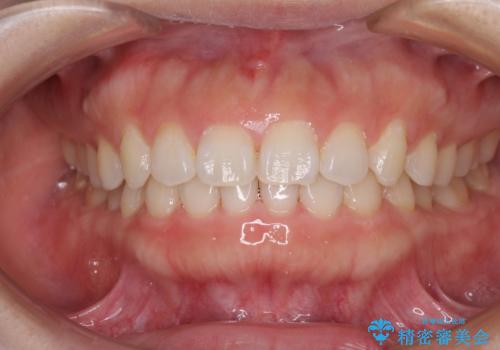

- ディープバイトを改善したいとのことで来院された患者様です。

カウンセリングの際には、下の前歯はほとんど隠れてしまっているような状態でした。

スクリューアンカーを用いて上顎歯列全体を後方に移動させるとともに、下顎の歯列を整えていくこととしました。

左右の臼歯は、当初1歯対1歯の咬合でしたが、終了時には理想とされる1歯対2歯に改善させることができました。

治療途中ではオープンバイトになってしまう局面もあるほど、患者様の気になっていたディープバイトをしっかりと改善することができました。